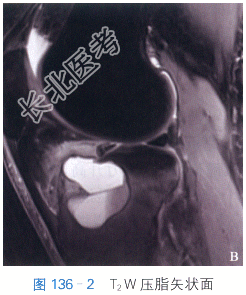

T₁W矢状面(见图136-1),胫骨平台多房性骨破坏,境界清楚,呈低信号影,病灶周围可见薄层线状更低信号影。T₂W矢状面脂肪抑制(见图136-2),病灶内见多房性伴“液液”平面。横断面STIR(见图136-3),病灶内见多房性伴“液-液”平面。

读片分析:该组案例MRI检查表现为胫骨平台局部膨胀,病灶呈多房改变,分隔较厚,病灶边界清。矢状面T₂W脂肪抑制可以看到病灶内部“液-液”平面,为动脉瘤样骨囊肿特征性表现。